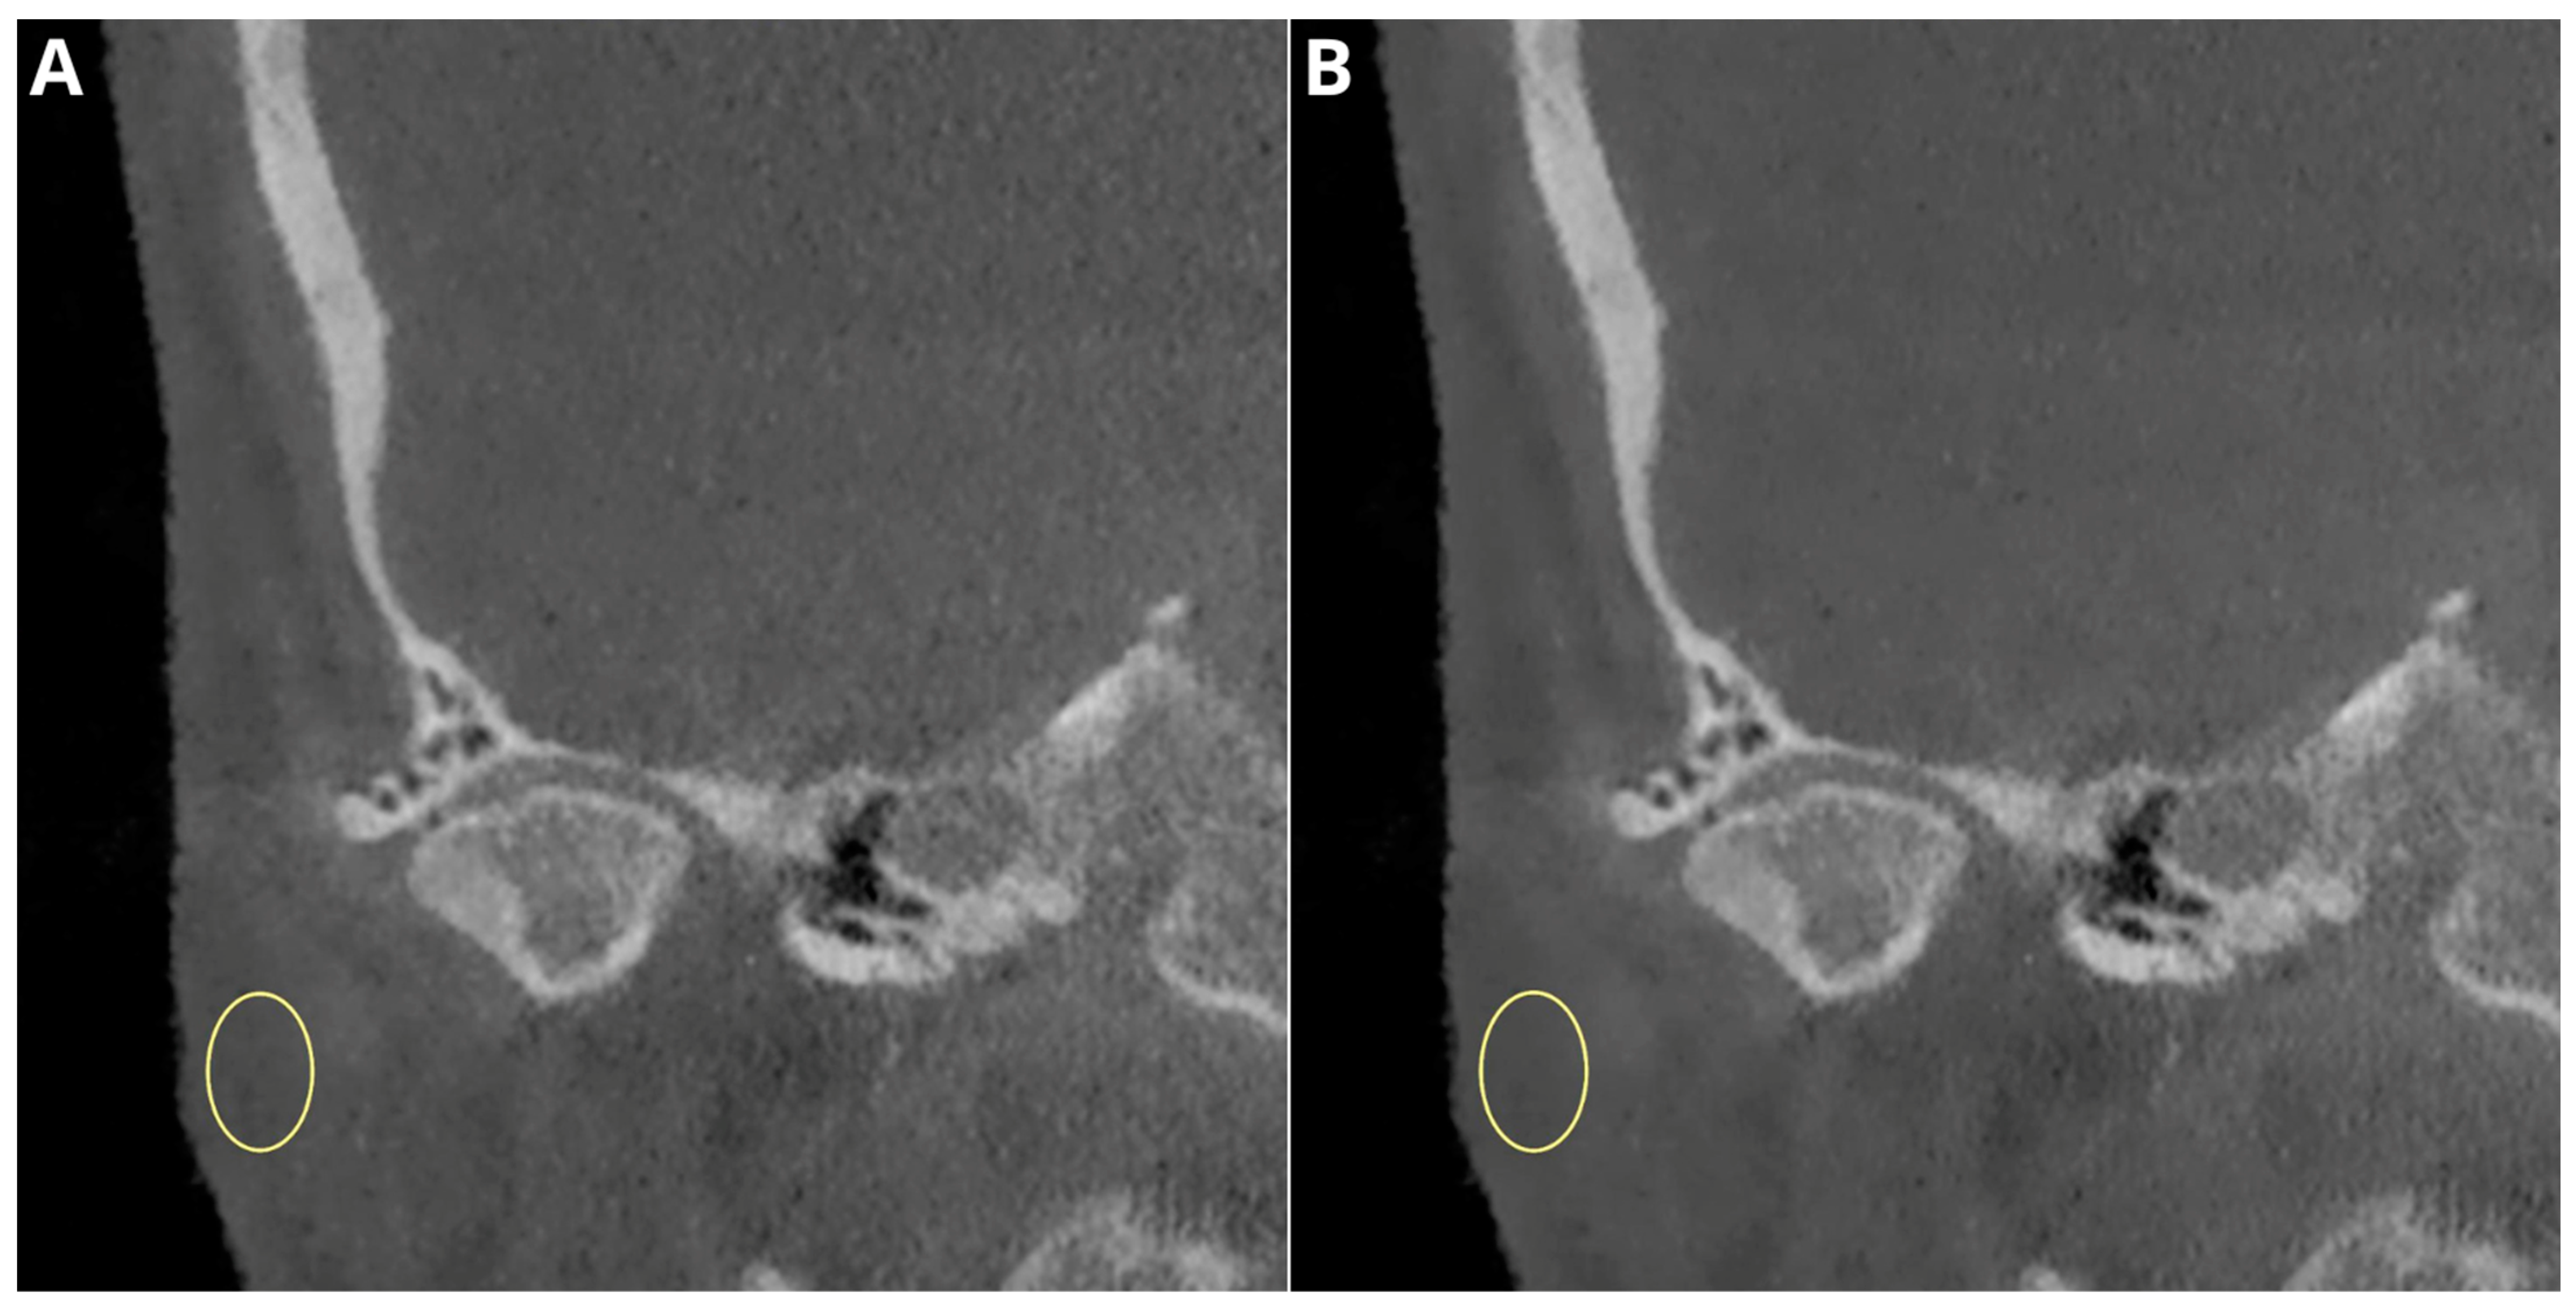

- flattening—the loss of the convex form of the articular surface;

- erosion and subchondral cysts—the loss of continuity in the cortical bone margins +/− cavities below the articular surface;

- osteophytes—marginal hypertrophy with sclerotic borders and the exophytic angular formation of the osseous tissue arising from the surface;

- subcortical sclerosis—an increase in the thickness of the cortical plate;

- condylar deformation—abnormal morphology of the condyle.